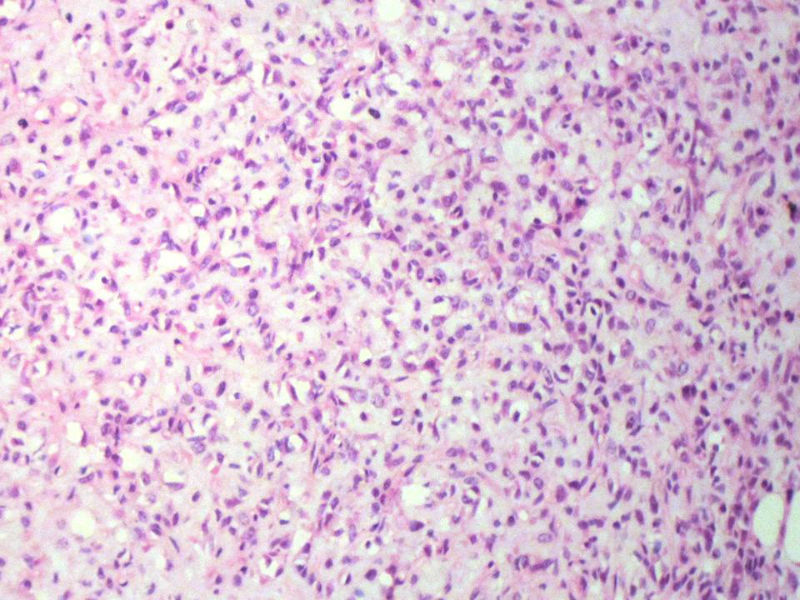

男,27岁,右股骨上段皮下肿物1年余,无明显疼痛,检查肿物明显隆起于皮下,边界清楚,手术完整切除肿物。肉眼,肿物6X6X5厘米,外观多结节状,似有包膜,切面灰白色,质韧。

特别提示:镜下核分裂3-4/HP.

3. 本例组织学改变与粘液性脂肪肉瘤,粘液样纤维肉瘤,纤维粘液样肉瘤,骨外粘液样软骨肉瘤都有重叠之处,且镜下并未见典型结构。由此,免疫组化结果就尤显重要。特别是专业书籍提到,突触素或嗜铬素阳性,对鉴别诊断有重要意义。我用CGA,也是在以上几个肿瘤中举棋不定而为。NSE和CK没用,其实我想用更多的抗体来证实更多的东西,但患者的经济条件不太好,遗憾!